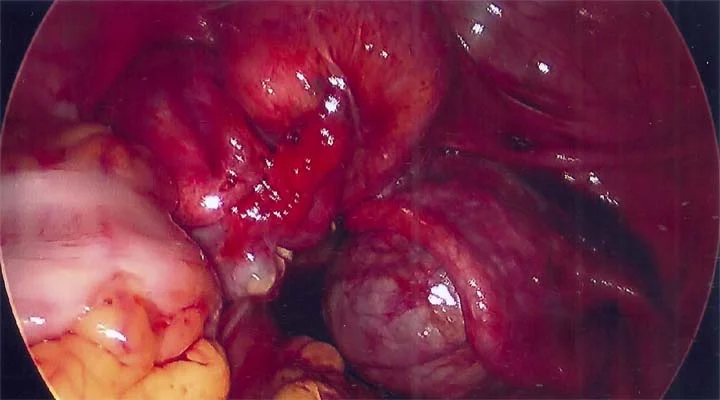

Right ovarian endometrioma is very adherent to right pelvic side wall

Close up of right ovarian endometrioma